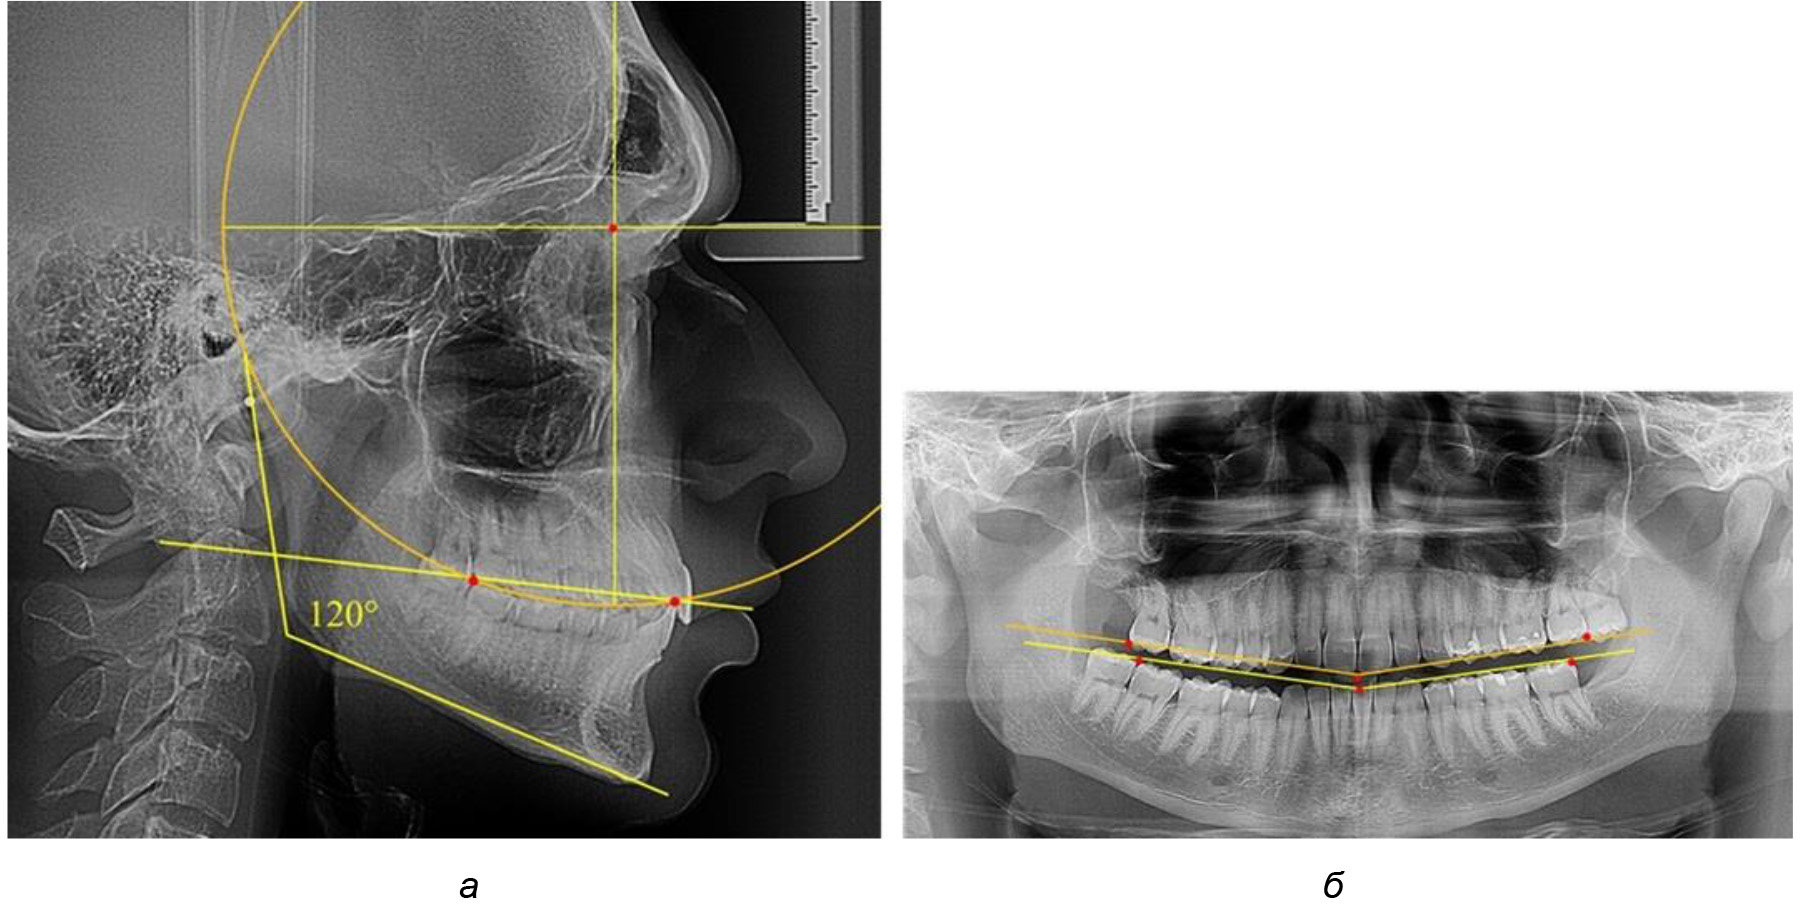

При анализе латеральных ТРГ устанавливали реперный окклюзионные точки в переднем и боковом отделе. Передняя точка устанавливалась на режущем крае нижнего медиального резца, которую в клинике ортодонтии обозначают как vPOcP. Дистальная точка второго нижнего моляра обозначалась как hPOcP. Измеряли расстояние между окклюзионными точками, что определяло сагиттальный размер окклюзионной линии. Использование программ PowerPoint позволило проводить окружность, проходящую по линии смыкания зубов через окклюзионные точки. Измеряли радиус окружности. Учитывая вариабельность размеров окклюзионной линии и радиуса окружности, определяли относительный показатель через отношение радиуса круга к длине сагиттального размера окклюзионной линии. Глубину окклюзионной кривой измеряли от точки наибольшей выпуклости до окклюзионной линии (рис. 1). На ортопантомограмме (ОПТГ) также соединяли окклюзионные точки правой и левой стороны и измеряли глубину окклюзионной кривой от точки наибольшей выпуклости до окклюзионной прямой линии. Результаты глубины кривой Spee сравнивали по данным ТРГ и ОПТГ.

Рис. 1. Метод определения кривой Spee на ТРГ (а) и на ОПТГ (б)

Анализ результатов показал, что глубина кривой Spee в среднем по подгруппе составил (4,12 ± 0,53) мм как при анализе ТРГ, так и ОПТГ.

Деление величины радиуса круга к длине окклюзионной линии составило 1,623 ± 0,02. Таким образом, для определения радиуса окружности, соответствующей кривизне окклюзионного контура боковой ТРГ, необходимо измерить расстояние между передней и задней окклюзионными точками и последующим умножением полученной величины на число Фибоначчи (рис. 2).

На рентгенограммах людей 2-й подгруппы (30 человек с нейтральным типом роста) величина угла нижней челюсти в среднем составила (120,34 ± 2,19) ° и характеризовала нейтральный тип нижней челюсти.

Глубина кривой Spee в среднем по 2-й подгруппе составил (3,54 ± 0,58) мм, что было незначительно меньше, чем при анализе аналогичного показателя 1-й подгруппы.

Достоверных различий с показателями, полученными при анализе ТРГ и ОПТГ, нами не отмечено (р ˃ 0,05). Деление величины радиуса круга к длине окклюзионной линии составило 1,612 ± 0,02, что, так же как и в 1-й подгруппе, было близким по значению к числу Фибоначчи (1, 618).